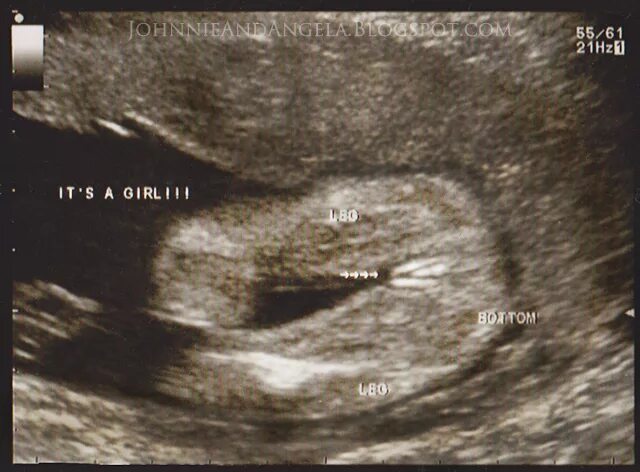

16 неделя можно ли узнать пол ребенка